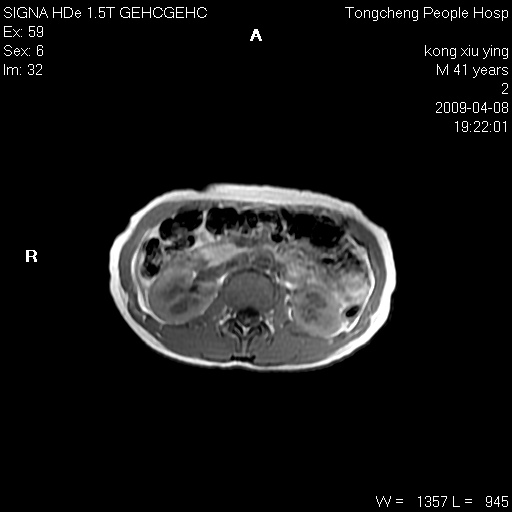

标题: CL1008:【经典】胆囊石榴籽样结石。 [打印本页]

标题: CL1008:【经典】胆囊石榴籽样结石。

女,41岁。健康体检——彩超提示:胆囊显示不清。平素健康,无不适感。

腹部mr扫描及mrcp,图像如下:

胆囊石榴籽样结石。